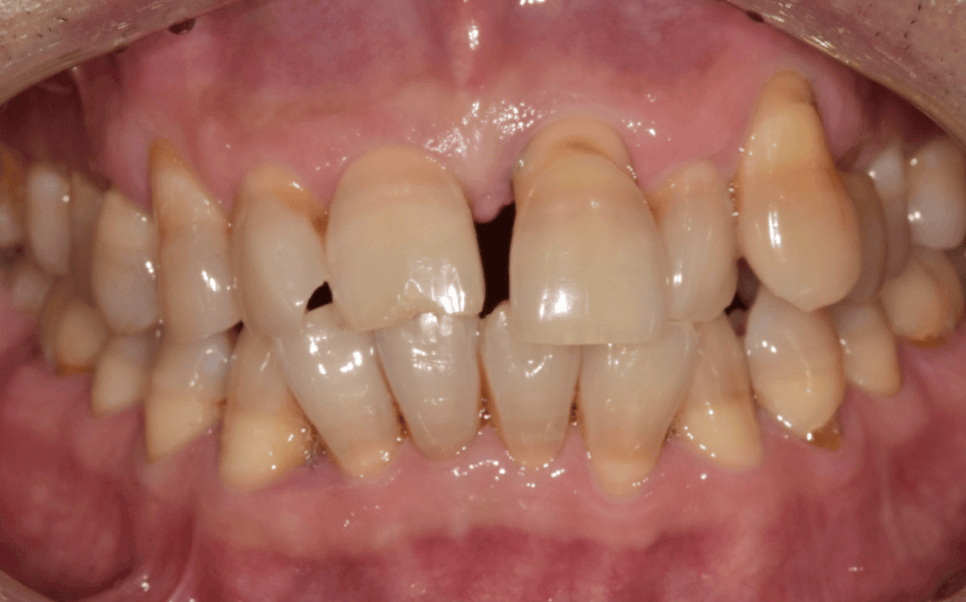

그렇게 해서 나온 최종 결과물.

230515

무엇보다 자연치아를 살릴 수 있어서 다행입니다.

230413(전) 230515 (후)